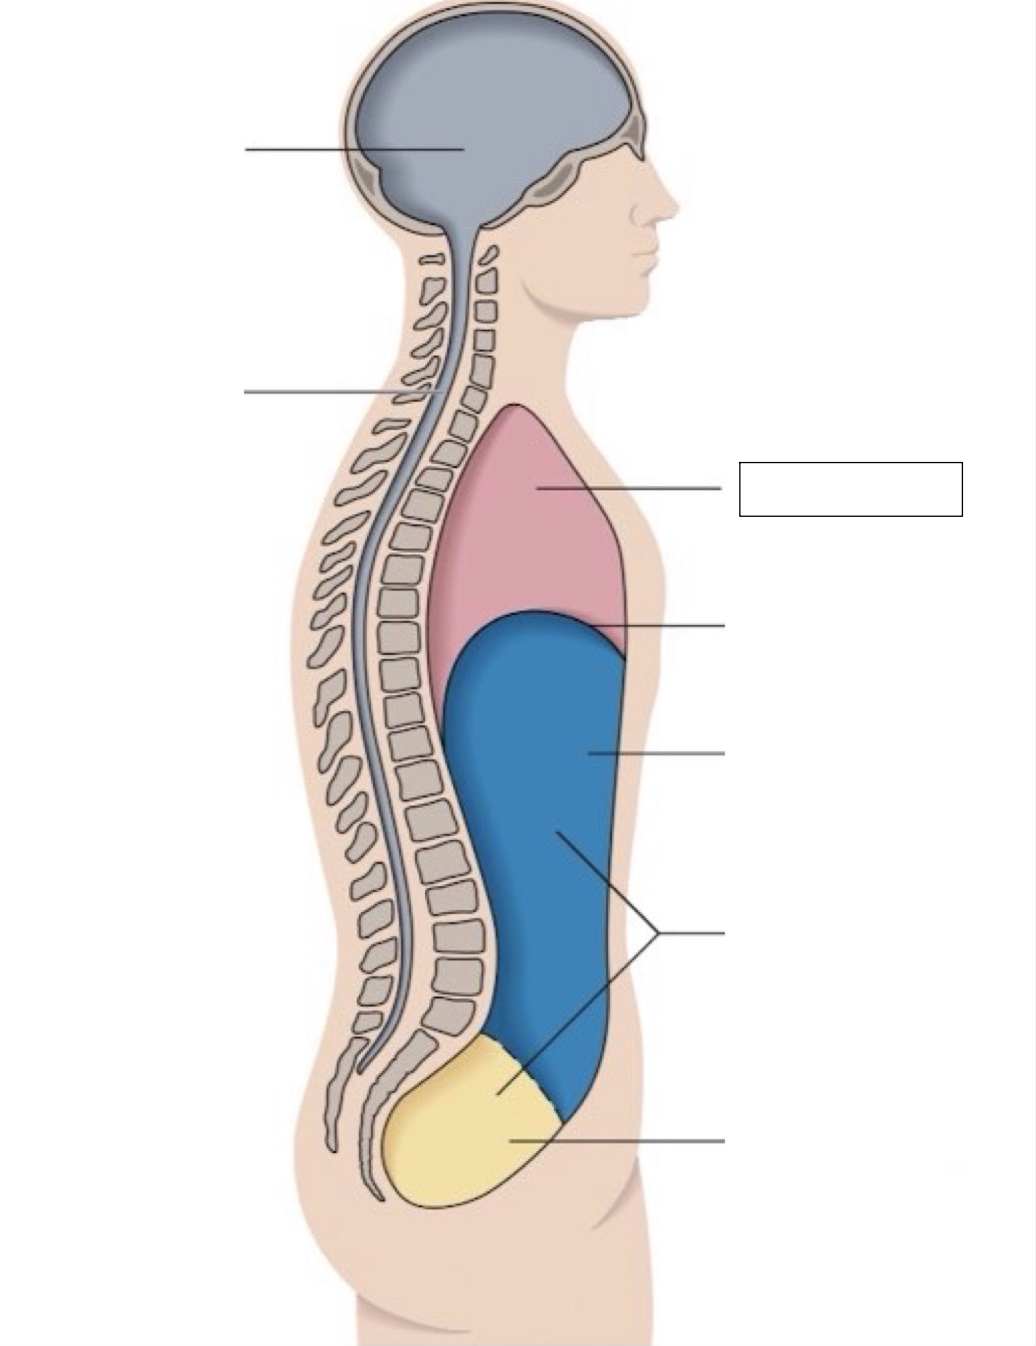

thoracic cavity

diaphragm

abdominal cavity

abdomino-pelvic cavity

pelvic cavity

spinal cavity

cranial cavity